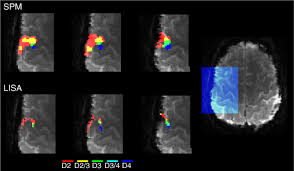

Influence Of Sample Size And Analytic Approach On Stability And Interpretation Of Brain Behavior Correlations In Task Related Fmri Data Grady 2021 Human Brain Mapping Wiley Online Library

Influence Of Sample Size And Analytic Approach On Stability And Interpretation Of Brain Behavior Correlations In Task Related Fmri Data Grady 2021 Human Brain Mapping Wiley Online Library from onlinelibrary.wiley.com